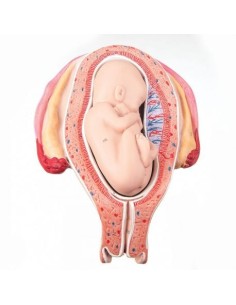

Dal cranio in 22 parti con incastri magnetici ai modelli di colonna vertebrale, da quelli di articolazioni a quelli di cuore, ogni pezzo della nostra collezione è progettato per un’immersione totale nello studio dell’anatomia umana. I nostri modelli, realizzati tramite scansioni di ossa vere, garantiscono un’esperienza tattile autentica e una fedeltà di peso quasi identica agli originali.

Essenziali per studenti e professionisti, i nostri modelli anatomici sono strumenti didattici che permettono di osservare le strutture anatomiche con precisione, eliminando la necessità di dissezioni o studi invasivi. Sono inoltre utili per spiegare ai pazienti le patologie, rendendo la comunicazione più efficace e risparmiando tempo prezioso.